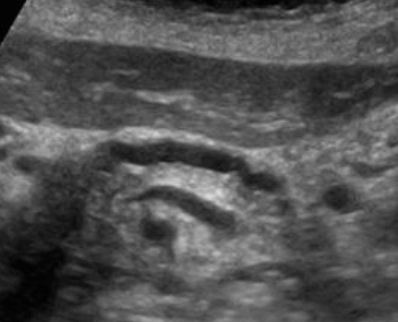

췌두부의 암 (Adenocarcinoma of head of pancreas) 담관낭종 (Choledochal cyst )

- 선천성으로 발생한 총담관의 낭종이고 가장 흔한 호발부위는 간문부이다.

- 간내담관 확장은 없거나 미미하다.

- 환자의 대부분은 10세 이전에 발생한다.

- 임상소견은 무증상이나 우상복부통증, 황달등이 나타날 수 있다

US finding

- 담관 내 무에코의 낭종

- 경계가 분명한 후방음향 증강

- 지방식 검사 후 수축소견이 없다.